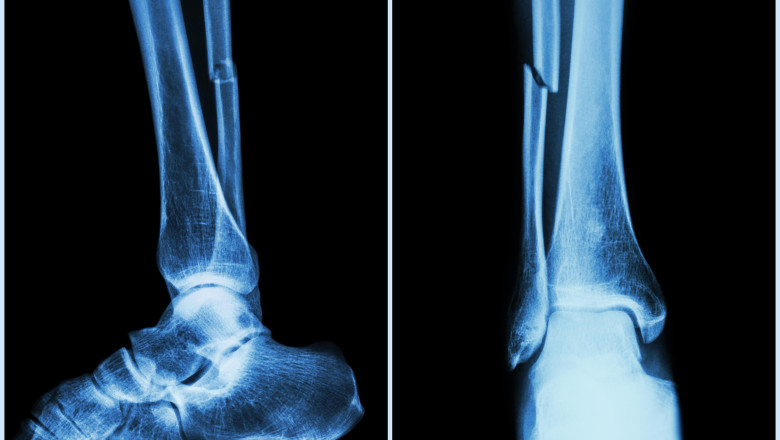

os fractura

Foto: Profimedia

Cercetătorii chinezi susţin că au dezvoltat un adeziv osos care poate fi folosit pentru a trata fracturile şi fragmentele osoase zdrobite, printr-o procedură care durează doar trei minute. Echipa de cercetare din provincia Zhejiang, sub conducerea medicului ortoped dr. Lin Xianfeng, de la spitalul Sir Run Run Shaw, din China, a anunţat că a dezvoltat un adeziv medical inovator care ar putea schimba radical modul în care sunt tratate fracturile, potrivit News.ro.

Substanţa, denumită „Bone-02”, promite să repare fragmentele de os în doar câteva minute, reducând necesitatea intervenţiilor chirurgicale invazive şi a implanturilor metalice.